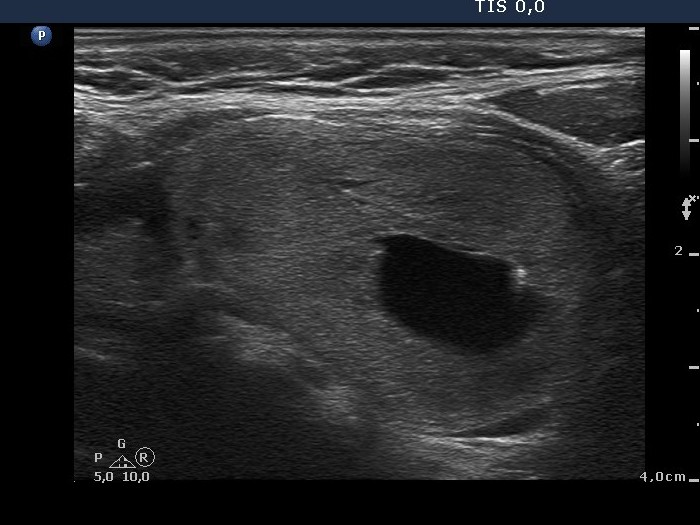

Follicular adenoma - Case 6. |

Clinical data: a 62-year old woman was presented with difficulties in swallowing.

Palpation: a nodule in the left lobe.

Functional state: euthyroidism with TSH 3.38 mIU/L.

Ultrasonography: the thyroids were echonormal. There was a moderately hypoechogenic and an echonormal lesion in the right lobe. The left lobe contained a large echonormal nodule. The nodule displayed a halo sign and perinodular blood flow and central cystic degeneration.

Cytology resulted in follicular tumor.

Histopathology disclosed follicular adenoma.